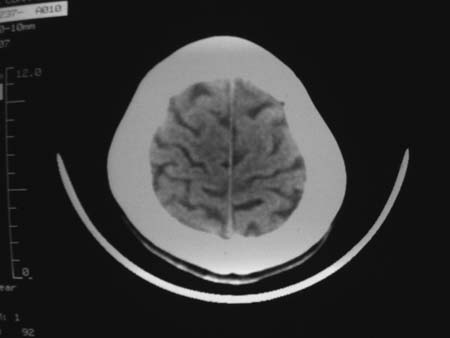

男,54岁,十天前被钢管打伤头顶部,现自述头部不适,视物模糊,并于两天前发觉右枕部有包块,既往未有明显异常.

颅骨多处骨质不完整,内板变薄,右侧额颞部局部呈“穿凿样”骨质缺损,相应区硬膜外密度略增高。多考虑:骨嗜酸性肉芽肿!

颅骨多处骨质不完整,内板变薄,右侧额颞部局部呈“穿凿样”骨质缺损,相应区硬膜外密度略增高。多考虑:骨髓瘤或骨嗜酸性肉芽肿!

颅骨多处骨质不完整,内板变薄,右侧额颞部局部呈“穿凿样”骨质缺损,缺损骨质边缘锐利无硬化,相应区硬膜外密度略增高。多考虑:骨嗜酸性肉芽肿!

颅骨多处骨质不完整,内板变薄,右侧额颞部局部呈“穿凿样”骨质缺损,相应区硬膜外密度略增高。多考虑:骨髓瘤或骨嗜酸性肉芽肿!10天前受伤,不会在2天前才发现头部包块,估计与外伤无关.